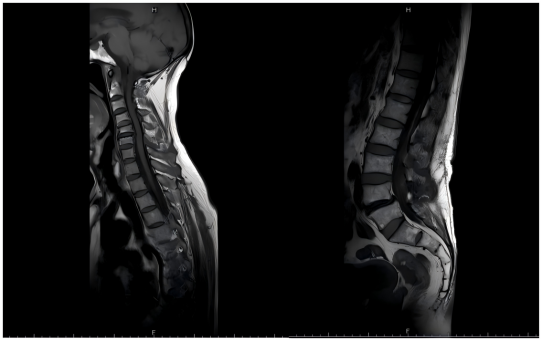

• MR:颈胸腰椎生理曲度正常,多个颈胸腰椎散在结节状及斑片状脂稍高信号,以T9明显,余序列未见显示。C4/5椎间盘轻度向后突出,椎管及双侧推间孔无狭窄。

3.png